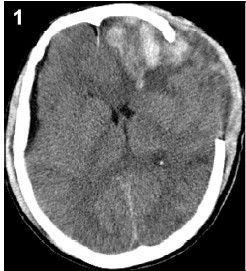

2.3 Subdural effusionSubdural effusion is another frequent complication secondary to DC (Figure 3),and also is a frequent complication after head trauma. Kinds of factors may lead to subdural effusion after DC. The large cranial defect after DC would form a pressure gradient between the two hemispheres and lead to the enlargement of ipisilateral subdural space as well as the accumulation of effusion,especially when initially there is a possible rupture in arachoid layer after head trauma[15]. Besides, the disturbance of cerebrospinal fluid (CSF) circulation after head trauma,especially the absticle of CSF out flow,would increase the risk of accumulation of the effusion through the torn portion of arachoid layer[15].

| Figure 3 The subdural effusion contralateral to the decompressive hemisphere can be seen from the CT, and it has mass effects and causes the compression of lateral ventricle. |